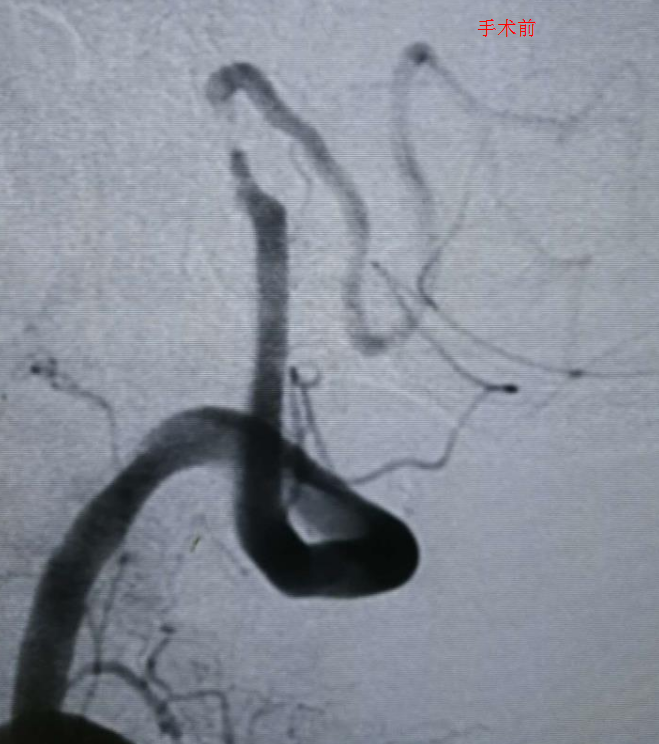

此时,南方医科大学深圳医院神经内科的学科带头人刘亚杰及其团队果断而及时的为病人选择了在介入下动脉支架取栓术。在惊心动魄、有条不紊的2个小时手术过程中,脑血管造影发现了闭塞的动脉血管,通过支架的方式撑开了闭塞的血管,接着再将堵塞血管的血栓拉出体外,闭塞的血管被打通,血流也恢复了供应。邹爷爷的神志恢复了正常,头晕很快就改善了,也转危为安。

刘亚杰介绍,诊断出病情的时候,邹爷爷发病已超过6小时,已经不适合静脉溶栓这一目前最有效的药物治疗方式。最新的卒中治疗指南建议,此时,应该对大脑动脉被大面积血栓堵塞的卒中患者行支架取栓,取出阻塞动脉血管的血栓。支架取栓是目前针对急性脑梗死最为有效的治疗方法,它是一种微创手术,通过支架将血栓直接从堵塞血管中取出,使闭塞血管快速再通,恢复大脑供血,降低患者的死亡率和致残率,改善患者以后的生活状态,可将血管开通率提高到80%。